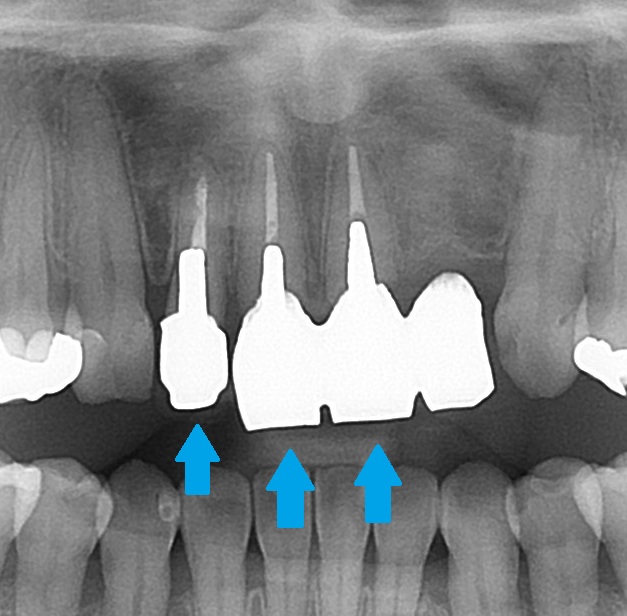

エックス線検査(レントゲン)で歯の中の状態を見てみると、

このような状態でした。

こちらの歯、3本が差し歯になっており、

後でお話しますが、メタルコアが入っています。

こちらの1本は歯が無く、ダミーの歯で繋がれています。昔に事故で抜いてしまったようです。